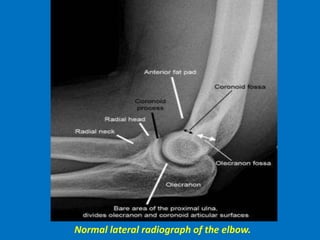

Normal lateral radiograph of the elbow.